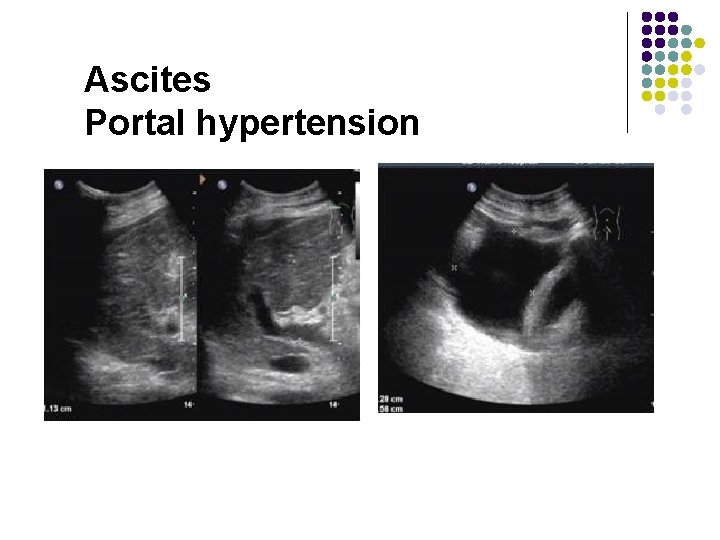

Ascites Portal hypertension

Ascites, even in very small qualities, can cause a thick gallbladder wall

Ascites